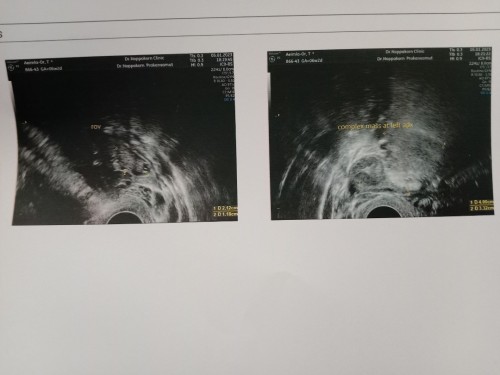

ตั้งครรภ์ได้ 6 w ซาวด์ทางช่องคลอดครั้งแรก หมอบอกว่ายังไม่เห็นอะไรเลย ผิดปกติไหมคะ เครียด กังวลมากค่ะตอนนี้ หมอนัดซาวด์อีกที วันพุธหน้า การรอคอยแบบไม่รู้จุดหมายมันทรมานมากจริงๆเลยค่ะ เครียดจนไม่อยากไปทำงาน วิตกกังวลทุกนาที เฝ้ารอคอยวันที่จะซาวด์ครั้งหน้าพร้อมกับความหวังว่าจะได้เจอตัวน้อยๆพร้อมหัวใจของเขา #ขอบคุณล่วงหน้านะคะ

ไข่อาจจะตกช้านะคะ คุณแม่ใจเย็นๆนะคะ ของเราตอนนี้6w6d เจอน้องพร้อมหัวใจเต้นแล้วค่ะ ตอนแรกซาวด์ก็เข้าใจว่าอายุครรภ์ตรงกับประจำเดือนเจอแต่ถุงตั้งครรภ์กับถุงไข่แดงตอน5wค่ะ แต่จริงๆแล้วประจำเดือนเราไม่ปกติเลยไข่ตกช้าค่ะ คุณแม่อย่าพึ่งกังวลมากนะคะ รอน้องหน่อยจ้าน้องยังเล็กอยู่

อายุครรภ์ยังน้อยค่ะ ของเราซาววันนี้10วีค4วันพึ่งเจอน้อง คอน 8วีคเห็นถุงครั้งแรก และตอนซาว6วีคไม่เห็นไรเลยถุงก็ไม่เห็น อย่ากังวลค่ะเดี๋ยวก็เห็น

อย่าเครียดนะคะคุณแม่ บ้านนี้ซาวด์ตอน6 วีคทางช่องคลอดไม่เจออะไรเหมือนกันค่ะ มาเจออีกทีตอน9วีคพร้อมได้ยินเสียงเต้นของหัวใจน้องด้วยค่ะ

ของเราไปมาเมื่อวานค่ะแม่6weekเจอแต่ถุงตั้งครรภ์ ยังไม่เจอตัวน้องหมอบอกนั้งตัวจิ๋วมากๆ หมอนัดอีกเดือนหน้าค่อยจะเจอ รอนะคะแม่ ใจเย็นๆ